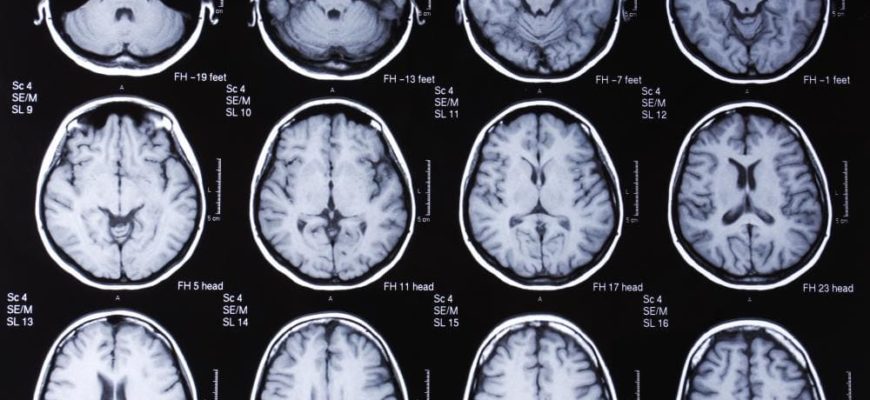

- МРТ — основана на действии магнитного поля, которое воздействует на атомы водорода в организме. Они меняют свой потенциал, а специальные сенсоры устройства улавливают сигнал и преобразуют его в изображение. На фотографиях показаны структуры головного мозга и патологические структуры. Во время процедуры пациент находится в капсуле аппарата, ему запрещается совершать малейшие движения, что снижает качество изображения.

Из сравнения видно, что МРТ отличается тем, что показывает органические изменения в головном мозге, ЭЭГ — физиологические процессы.

В магнитной томографии врач анализирует изображение и после энцефалограммы расшифровывает график.

Магнитно-резонансные изображения позволяют детально рассмотреть органическую патологию, не могут выявить физиологические нарушения.